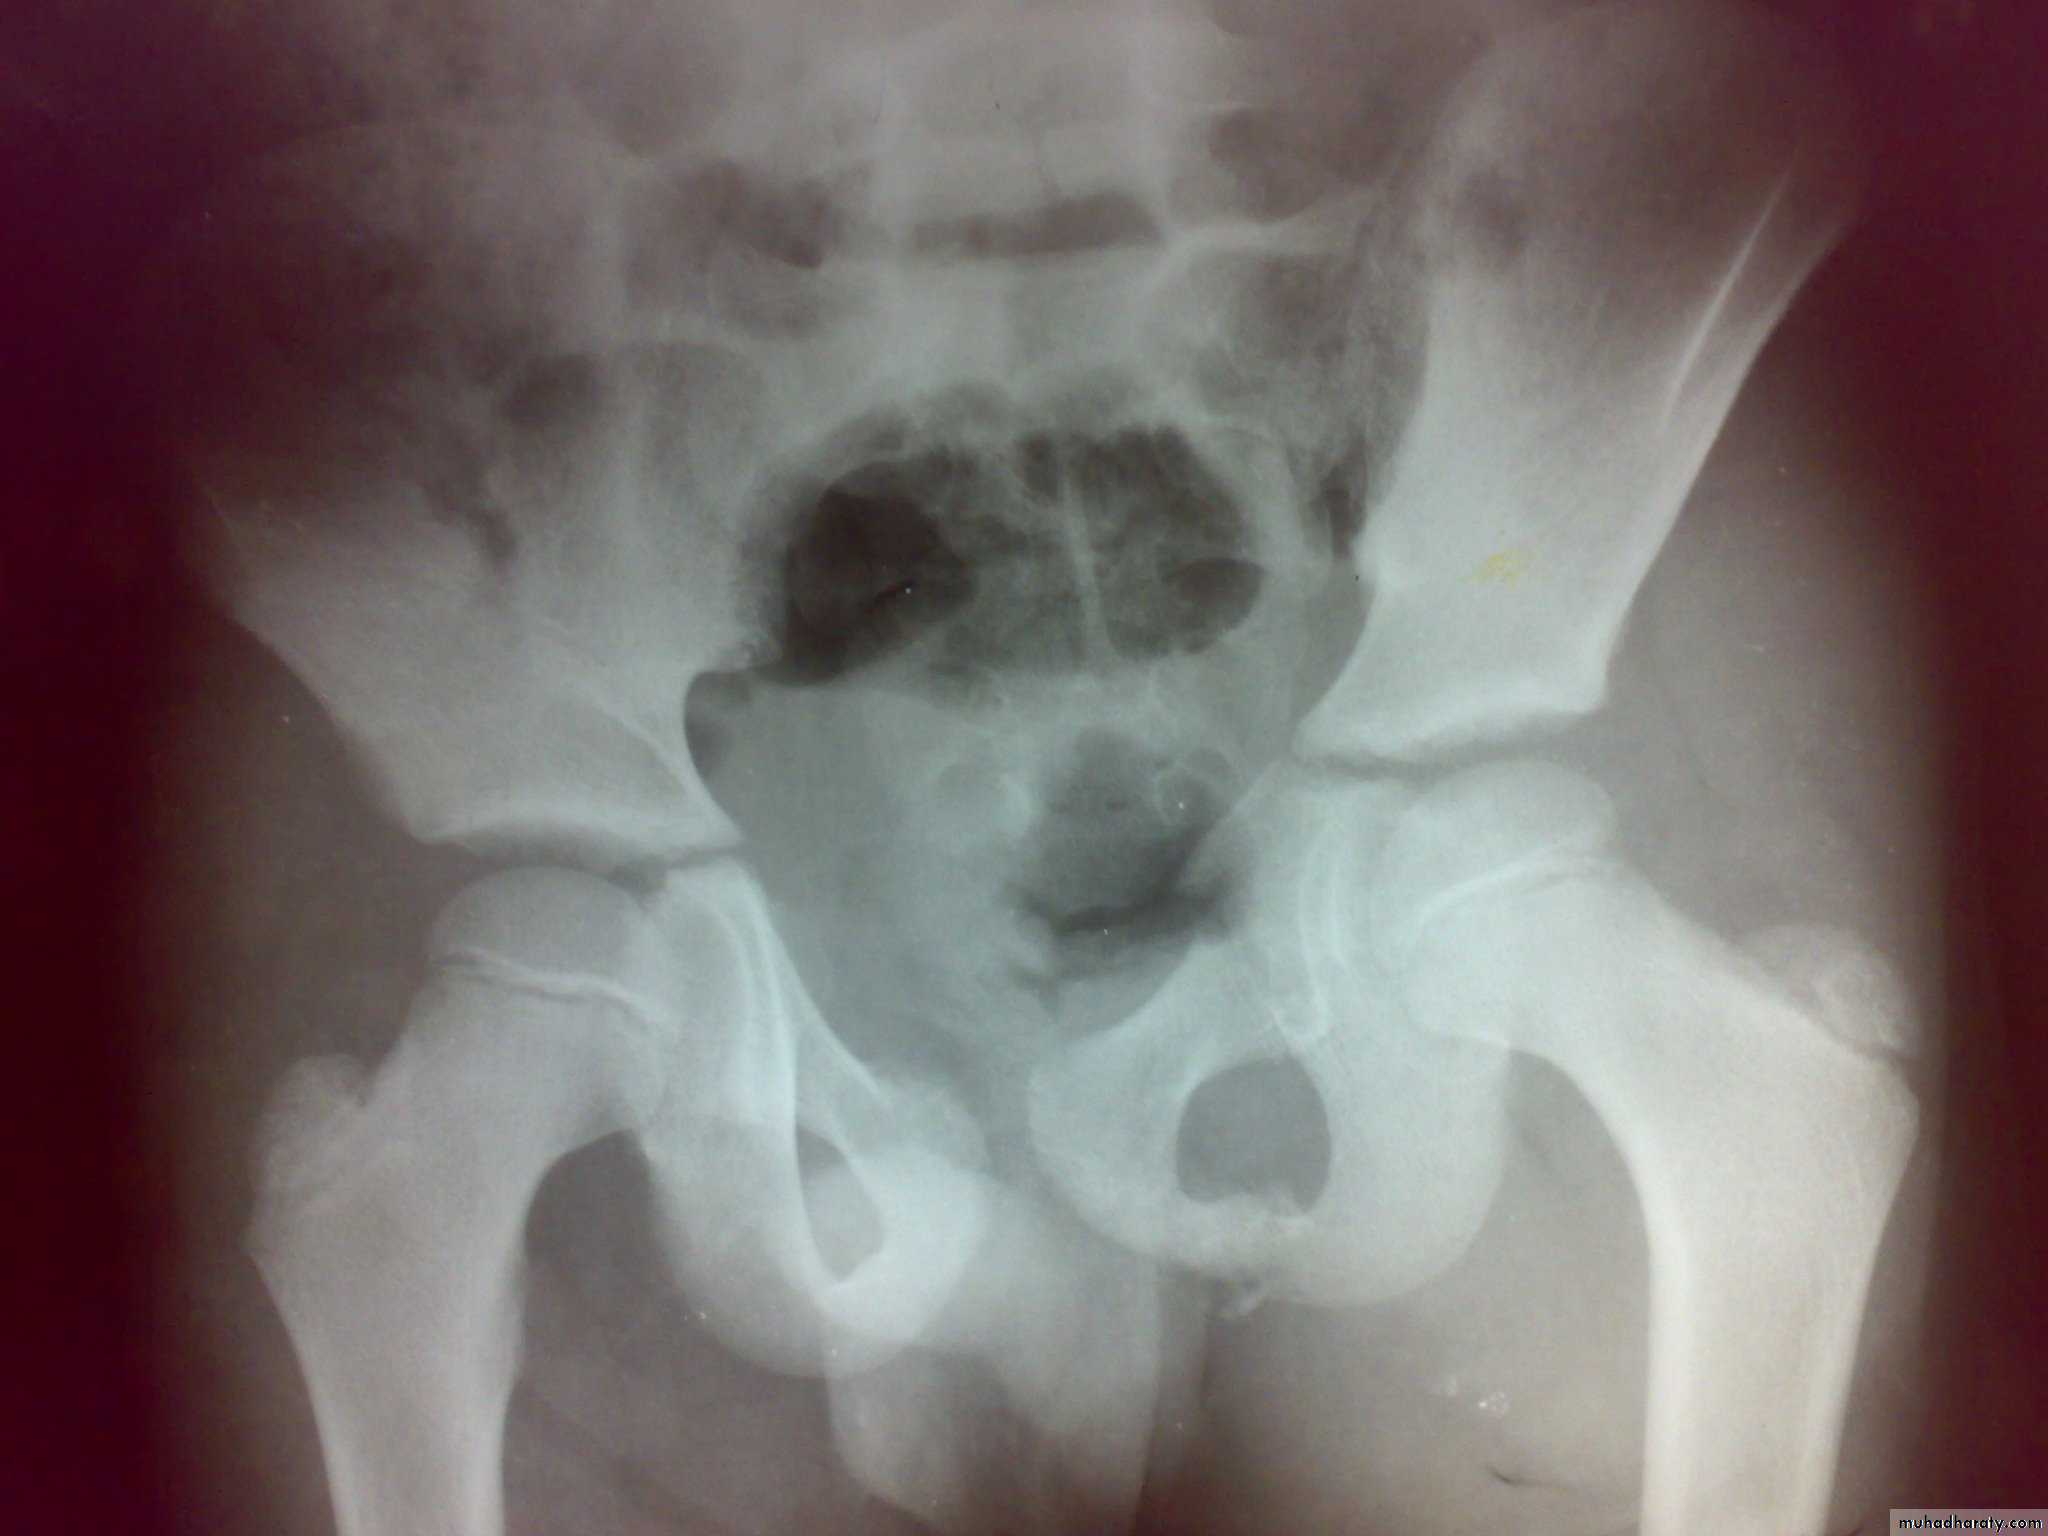

Fracture pubic ramai

Fracture pubic ramiFracture acetabulum

Unstable ring fractures

Caused by sever trauma.Extremely serious.

Carries high risk of visceral injuries.

There are fractures around or separation of symphysis pubis or sacroiliac joint.